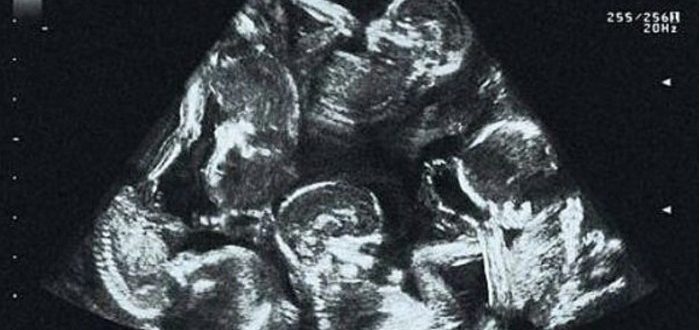

Moja žena je lagala o terminu porođaja kako ne bih propustio porođaj – kada sam saznao, skoro sam se srušio

Celog života sam želeo da budem otac. U četrdesetoj godini sam gledao kako deca mojih prijatelja prave svoje prve nesigurne korake, kako očevi pokušavaju da obuzdaju suze prvog